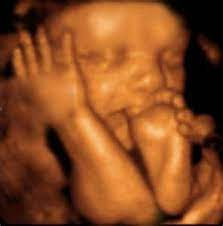

NUESTROS SERVICIOS

30 min

90.000 pesos colombianos15 min

90.000 pesos colombianos45 min

110.000 pesos colombianos45 min

150.000 pesos colombianos45 min

200.000 pesos colombianos45 min

130.000 pesos colombianos45 min

160.000 pesos colombianos45 min

250.000 pesos colombianos